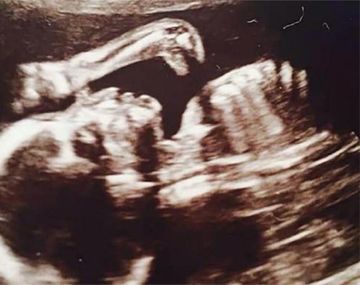

Encuentran un dinosaurio en una ecografía La curiosa situación se desató luego de realizar los estudios correspondientes para la llegada de Ruthie, la beba que espera la británica Leanne Sullivan. La mujer, luego de ver las imágenes, se llevó una gran sorpresa. Reino Unido